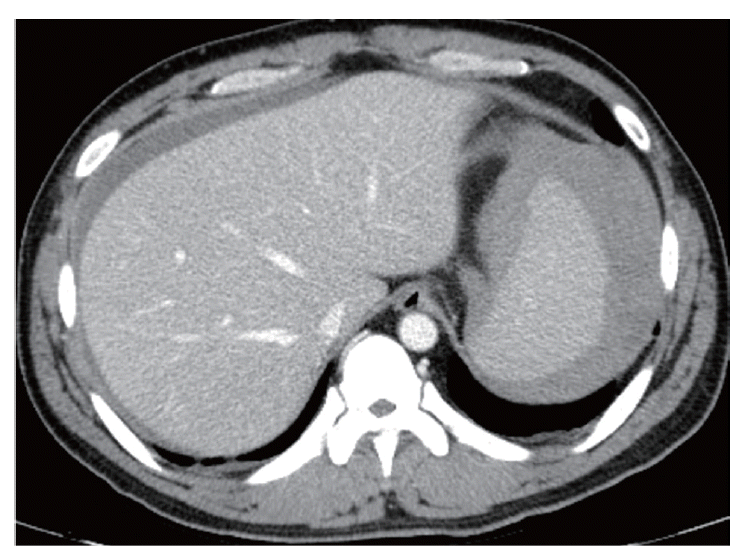

A follow-up CT was performed 5 days after the coil embolization. At this time, a reduced splenic subcapsular hematoma was observed. Several peripheral wedge-shaped low attenuated lesions were also found in the spleen, suggesting splenic infarction resulting from the coil embolization (Fig. 5). Hemoglobin levels were normalized (13.9 g/dl). After discharge, the patient has been closely followed-up at the Outpatient Department of Inha University Hospital. No other complications have developed.